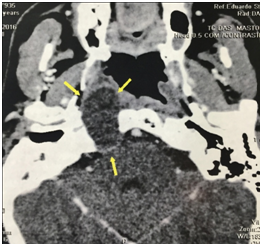

A 43years old man presented with 6month history of intermittent right hemicranial headache and ipsilateral conductive hearingloss. The patient had no historyof head trauma. The MRI demonstrated a large and expansile right petrous apex lesion hyper intense on both T1- and T2-weighted scans, without diffusion restriction or internal contrast enhancement. The CT scan showed and expansile and lyticlesion with surrounded bony erosion (Figures 1-4).

Figure 2 Preoperative axial contrast CT with a right expansile and lyticpetrous Apex lesion with bony erosion.